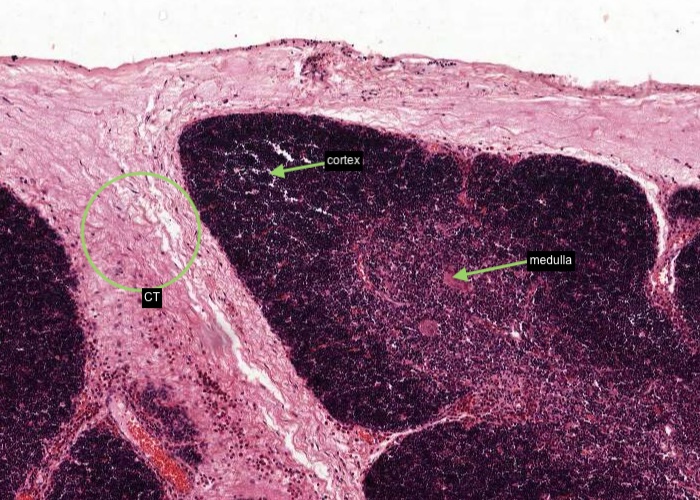

The thymus has extremely sophisticated functions but they are not reflected in structure visible on routine histological sections. You will be able to distinguish only two classes of cells, thymocytes (T cells) and epithelial reticular cells. Examine this section grossly and note that it is divided into lobules, each with a darker-staining cortex and lighter-staining medulla.

The thymus has a connective tissue capsule with septa of connective tissue that separate the lobules of the thymus and invests them with thin seams of connective tissue. Arteries enter the thymus through the capsule and arterioles leave the septa to penetrate the parenchyma. Medullary veins penetrate the connective tissue septa and leave the thymus through the capsule.

The seams (trabeculae) of connective tissue separate the lobules of the thymus. Identify the lobule cortex and lighter-stained medulla.

Note at low/medium magnification lobules, each with a darker-staining cortex and lighter-staining medulla and invested by seams of connective tissue penetrating from the capsule.

This image shows an area of the section dominated by the darker-staining cortex. Connective tissue invests each lobule of the thymus. Many blood vessels (identified by having their lumens filled with red blood cells) are within septa of connective tissue before they divide into smaller arterioles and capillaries to enter the cortex and medulla of each lobule.